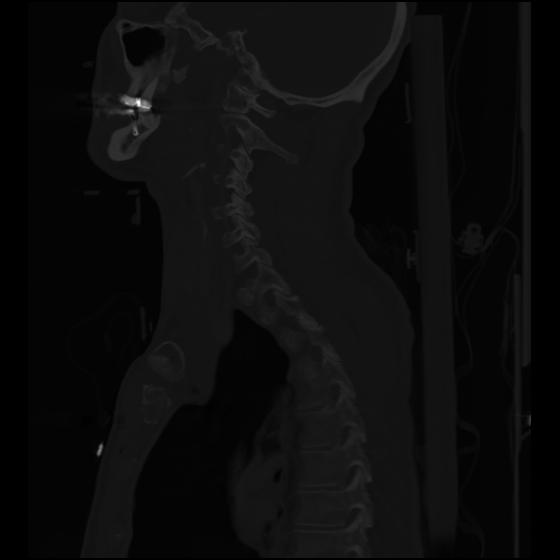

24 ANGIO,CE,Sag-MIP,5.000,ANGIO,Sag-MIP,